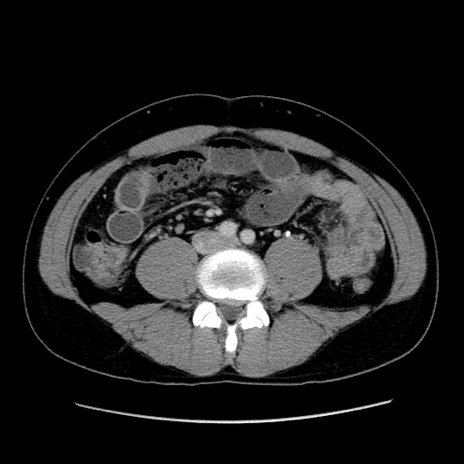

症例4(横断像)

【症例】30歳代男性

【主訴】腹痛、嘔吐

【現病歴】昨晩から突然の腹痛あり、その後嘔吐、軟便も出現。腹痛が改善しないため救急搬送となる。2日前にしめ鯖の食事歴あり。

【身体所見】意識清明、苦悶様、BP 135/90mmHg、BT 35.7℃、腹部:平坦、やや硬、心窩部〜臍部に自発痛、圧痛あり、筋性防御+、反跳痛-

【データ】WBC 8100、CRP 0.57